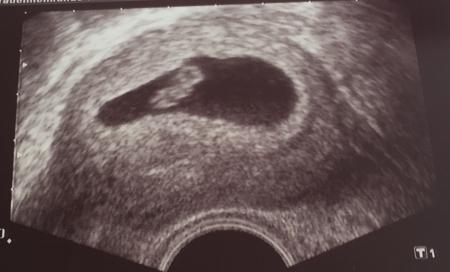

Hi Herzlichen Glückwunsch:-) Ich bin auch noch ganz frisch dabei, war gestern beim FA, da hat man nun endlich mal was gesehen, war sehr schön :-)